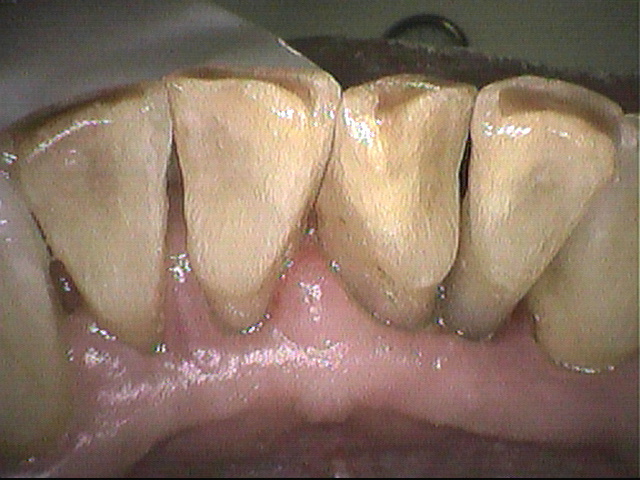

クリーニング後

3ヵ月毎にクリーニングにいらしている患者さんです。

下の前歯に歯石と磨き残しがありましたが

しっかり除去して綺麗になりました。

セルフケアをがんばっていても、人によっては歯石が多くついてしまうことがあります。

歯ブラシでは除去できませんが、ついたままになっていると

歯周病の原因となってしまうので、定期的にクリーニングをしましょう。